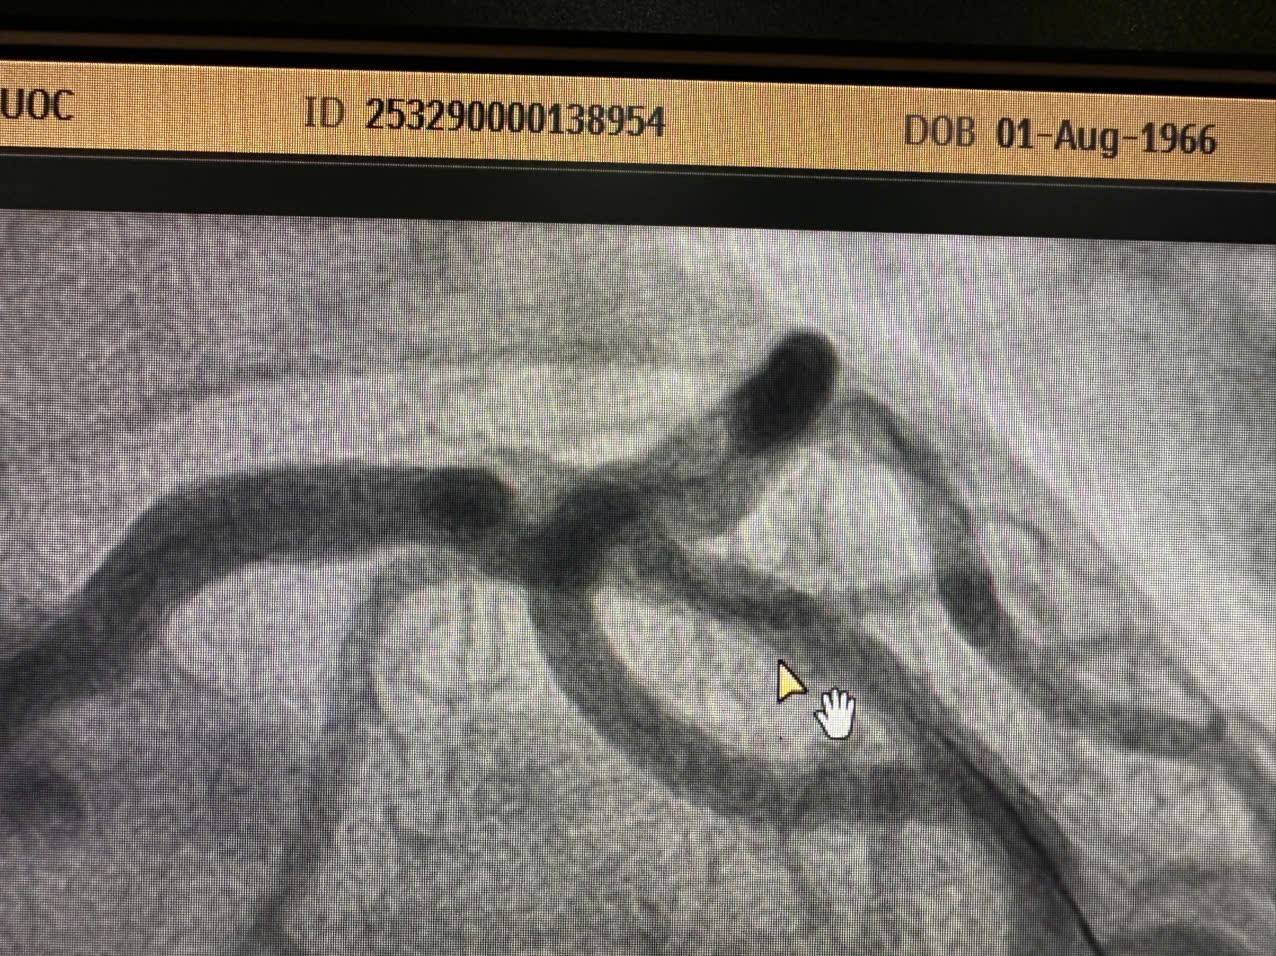

Ca thứ nhất – Nhồi máu cơ tim cấp ST chênh lên vùng trước rộng

Bệnh nhân nam, 62 tuổi, vào viện vì đau ngực trái giờ thứ nhất.

Chẩn đoán xác định: Nhồi máu cơ tim cấp ST chênh lên vùng trước rộng – tình trạng tối cấp cần tái tưới máu khẩn cấp.

Chụp mạch vành qua da ghi nhận:

Ê-kíp can thiệp đã tiến hành đặt 01 stent tái tưới máu thành công.

Sau can thiệp: mạch vành tái thông tốt, huyết động ổn định, bệnh nhân được chuyển về Khoa Tim mạch tiếp tục theo dõi.